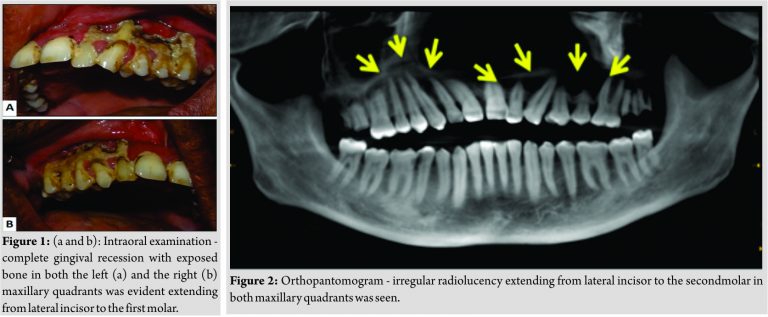

A 46-year-old male patient reported with complaint of pain in upper jaw region for1 year. There was a history of dengue fever with resulting leukopenia and thrombocytopenia 14-month back. The patient was positive for NS1 antibodies which are diagnostic for dengue infection [2]. 2-month after episode of dengue fever patient experienced swelling of gums followed by recession exposing underlying bone. There was no history of prolonged medication, drug allergy, and any dental treatment. On clinical examination, intraorally (Fig. 1a and b), there was complete gingival recession with irregular exposure of alveolar bone and a part of basal bone in both the left and the right maxillary quadrants extending from lateral incisors to the first molar. Root pieces of 27, 28, and 17 were evident. The patient’s oral hygiene was poor. Orthopantomogram revealed irregular radiolucency involving alveolar bone and basal bone in both maxillary quadrants in the region of lateral incisor and the second molar (Fig. 2).